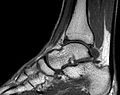

Bildgalerie

-

MRT des Sprunggelenks in T1-Wichtung -